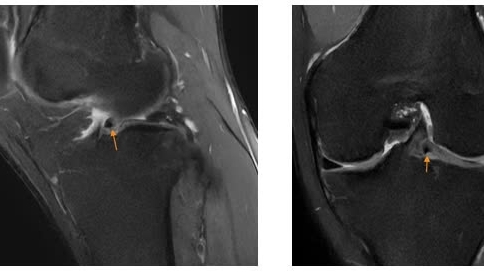

Hiện số lượng trẻ mắc các bệnh hô hấp đang có xu hướng gia tăng, trong đó có nhiều trẻ mắc cúm B. Nhiều cơ sở nhi khoa quá tải bệnh nhân tới khám.

Mặc dù cúm B là một trong những chủng cúm mùa phổ biến ở nước ta và xảy ra hàng năm, nhưng không phải cha mẹ nào cũng hiểu đúng và đủ về bệnh, dẫn đến tâm lý chủ quan hoặc hoang mang lo lắng quá mức.

Đáng lo ngại, nhiều gia đình tự ý làm xét nghiệm khi không cần thiết, gây lãng phí tiền bạc, hay sử dụng các loại thuốc không đúng làm ảnh hưởng đến sức khoẻ của trẻ…

Đặc biệt, vừa qua thông tin về ổ dịch cúm B với hàng trăm trẻ mắc tại huyện Chợ Đồn, Bắc Kạn đã khiến nhiều người không tránh khỏi lo lắng về dịch cúm B, nhất là khi trong gia đình có trẻ có các dấu hiệu ho, sốt…